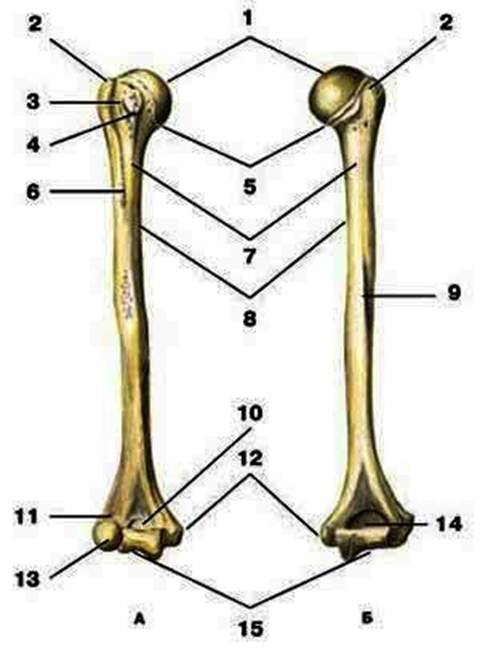

S: Цифра 1 обозначает головка плечевой кости.

S: Число 15 обозначает блок плечевой кости.

S: Цифра 5 указывает на хирургическая шейка плечевой кости.

S: Число 10 обозначает венечная ямка плечевой кости.

S: Число 14 указывает на локтевая ямка плечевой кости.

S: Цифра 9 указывает на борозда лучевого нерва плечевой кости.

S: Число 12 обозначает медиальный надмыщелок плечевой кости.

S: Стрелка указывает на большой бугорок плечевой кости.

S: Стрелка указывает на малый бугорок плечевой кости.